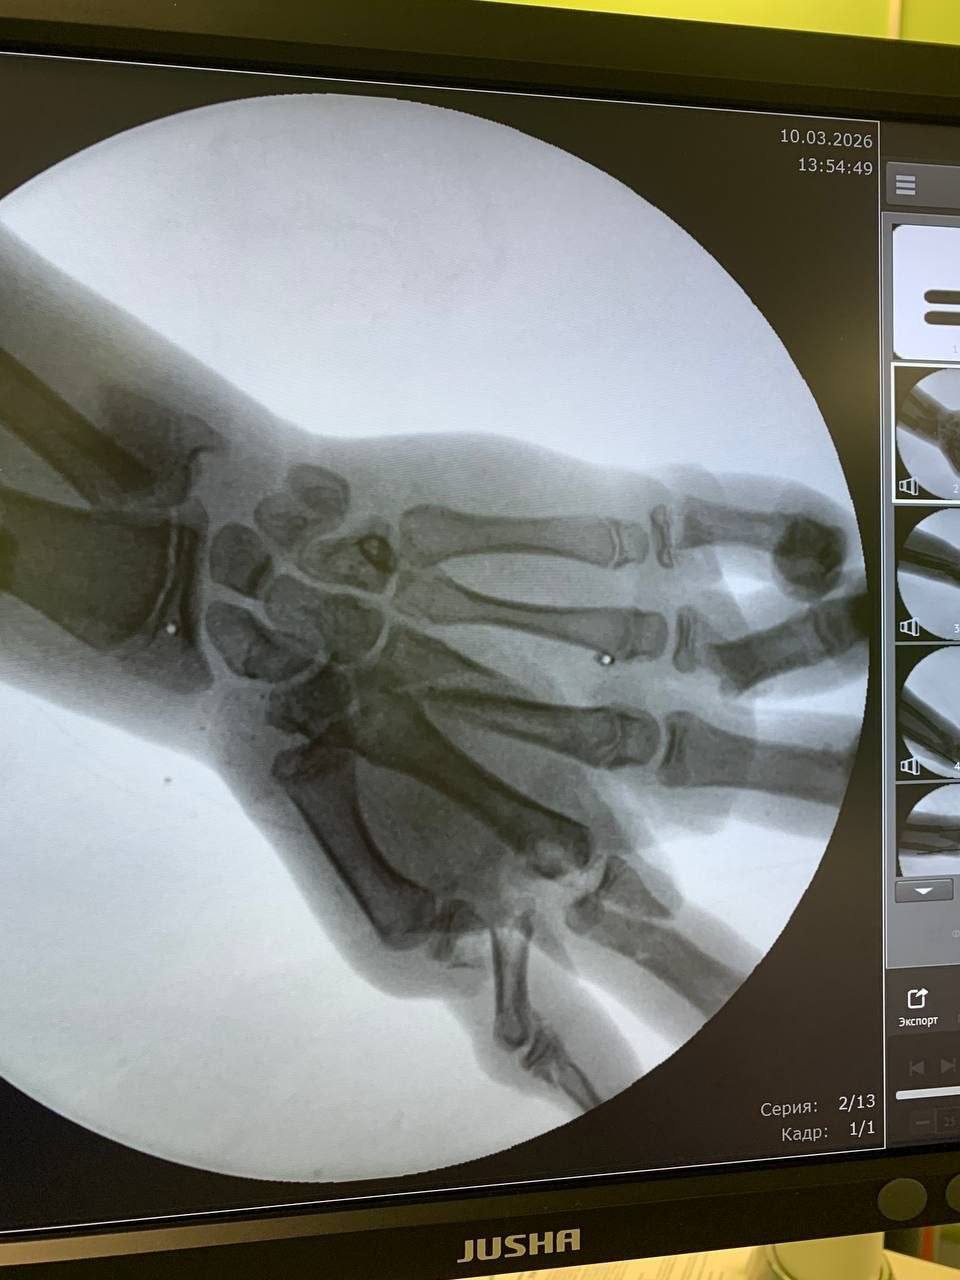

Пострадавшего доставили в больницу в шоковом состоянии. Врачи диагностировали перелом нижней трети левого предплечья со смещением, раны на голени и лбу, а также тяжёлые повреждения кисти с множественными переломами и сильным кровотечением. Существовал высокий риск потери части конечности.

Первую операцию провела бригада травматологов — Александр Гозун, Геннадий Петров и Артём Чабан. Противошоковую помощь обеспечивал анестезиолог Виктор Берг. За полтора часа врачам удалось остановить кровотечение, предотвратить инфекцию и восстановить положение костных фрагментов. Ключевой задачей стало сохранение кровотока в кисти.

«Поэтому чтобы правильно выстроить дальнейшую стратегию лечения, необходимо было выждать время, – объяснил Александр Гозун. – В итоге через несколько суток, оценив зону некроза, которая благодаря своевременно обеспеченному кровотоку в кисти оказалась небольшой, мы провели мальчику вторую, восстановительную операцию. Во время нее с помощью пластики были устранены дефекты тканей и костей».